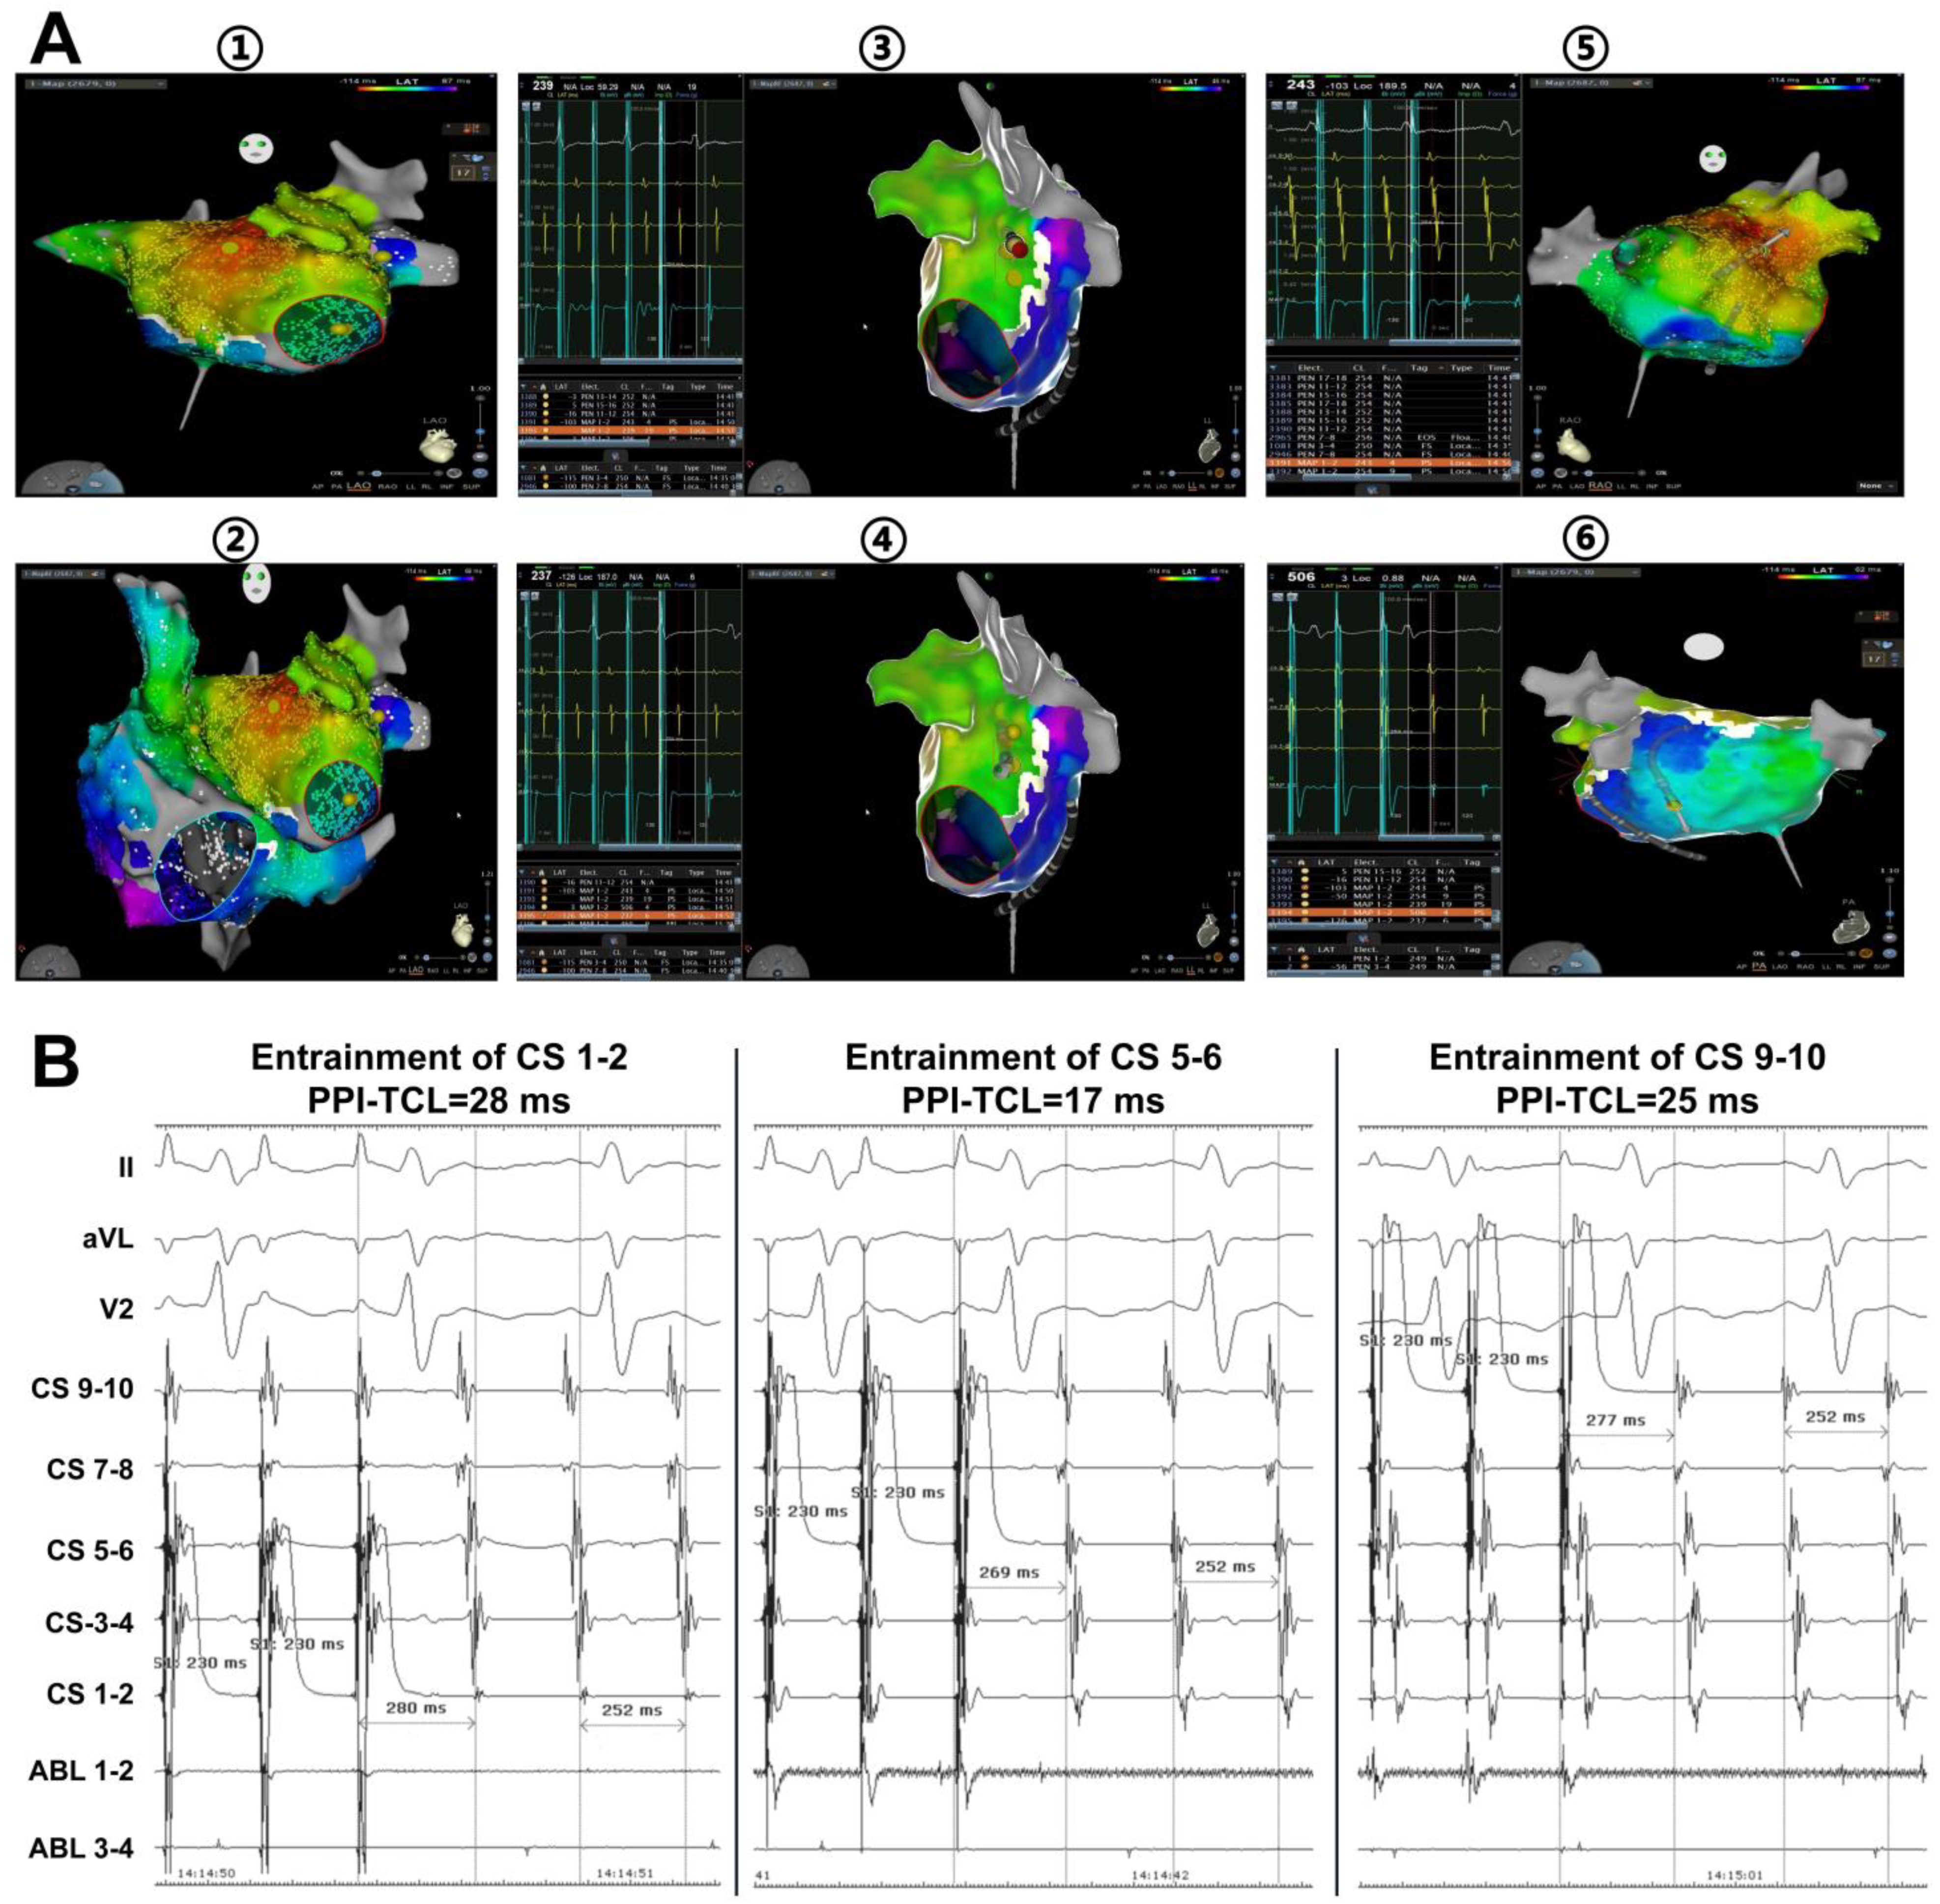

5. LOM/VOM as Epicardial Connection Mediates Perimitral Flutter after AF Ablation

6. The Challenge and Importance of MI Block

7. The Role of VOM Ethanol Infusion in PeAF Ablation